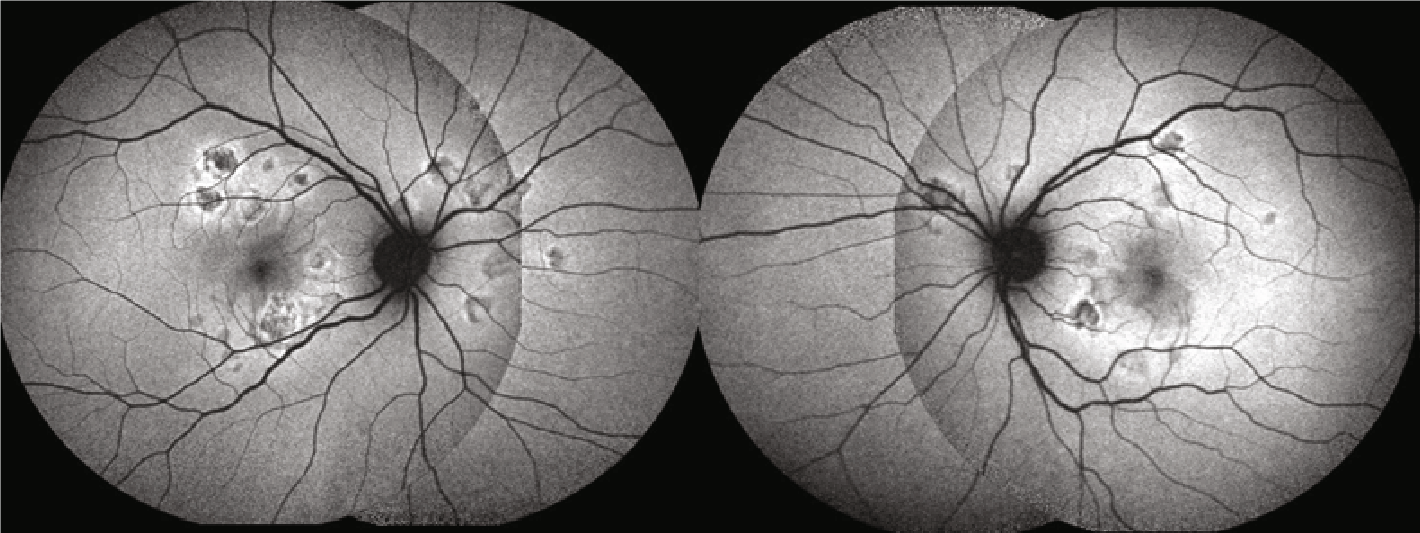

Fundus autoflourescense: hypoautofluroescent lesions with edges that are hyperautofluorescence (Copyright © 2020 Mariana A. Oliveira et al. Reproduced without modifications from an open access article, Management of Acute Posterior Multifocal Placoid Pigment Epitheliopathy (APMPPE): Insights from Multimodal Imaging with OCTA, distributed under the Creative Commons Attribution License; https://www.ncbi.nlm.nih.gov/pmc/articles/PMC7094199/)